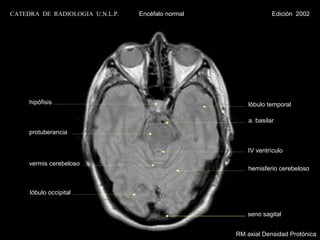

CATEDRA DE RADIOLOGIA U.N.L.P.   Encéfalo normal                Edición 2002

seno maxilar

clivus

a. carótida interna

bulbo

vermis cerebeloso

hemisferio cerebeloso

RM axial Densidad Protónica